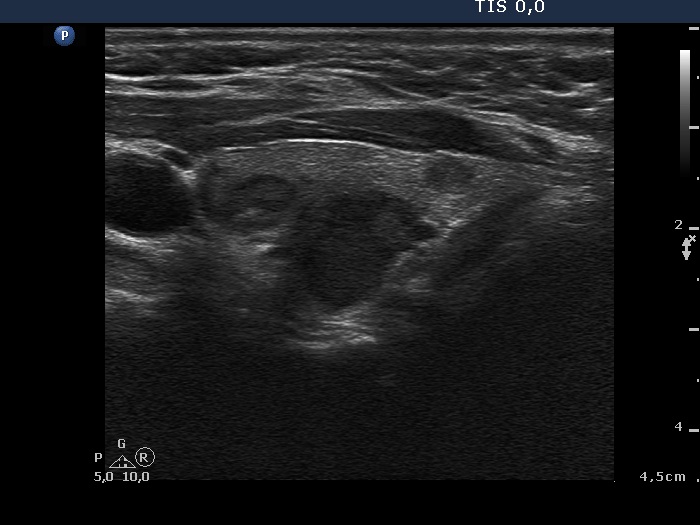

Ultrasonography. The right lobe was moderately hypoechoic while the left was echonormal. A large, less hypoechoic nodule occupied almost the entire right lobe. The nodule presented many hyperechogenic granules and line which corresponded to fibrosis. There were multiple small hypoechogenic lesions in the left lobe.